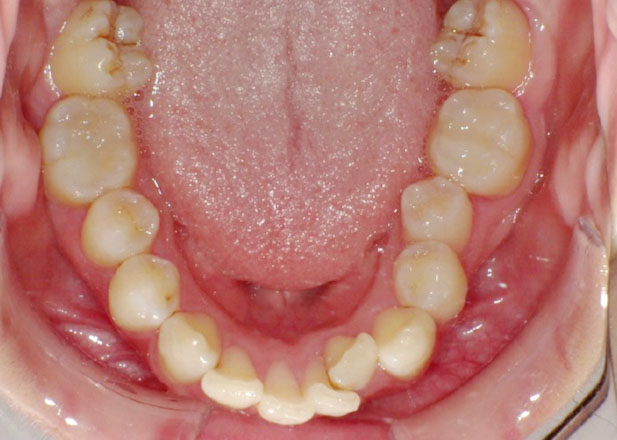

治療前

マウスピース矯正 マウスピース矯正 マウスピース矯正

口腔内写真

かみ合わせを治したい

かみ合わせの不調により痛みも生じている状態でしたが治療後は痛みをなく経過良好です。

今回は前から4番目の歯を1本抜歯して治療を行いました。

必ずしも歯を抜かないと矯正治療ができないというわけではありませんが「笑顔やお顔とのバランス」を考慮し、今回は抜歯を提案させていただきました。